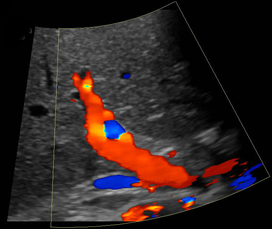

The UCSF ultrasound subspecialty performs the full array of ultrasound procedures, from general abdominal and fetal ultrasonography to the most advanced techniques, including color-flow doppler scans, ultrasonographically guided biopsies and aspirations, and endovaginal and endoscopic studies.

All UCSF ultrasonography facilities are equipped with the most up to date high resolution 2D, 3D, 4D grayscale and color-flow doppler scanning equipment.